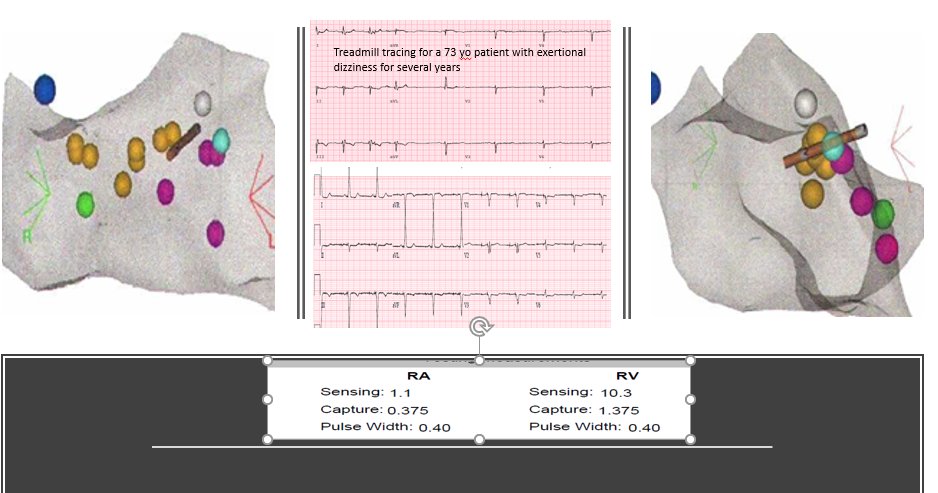

65 yo with symptomatic multifocal PVCs, ~30K, EF 45%,  3 different PVCs were ablated today..fun & require patience, thanks to the team!